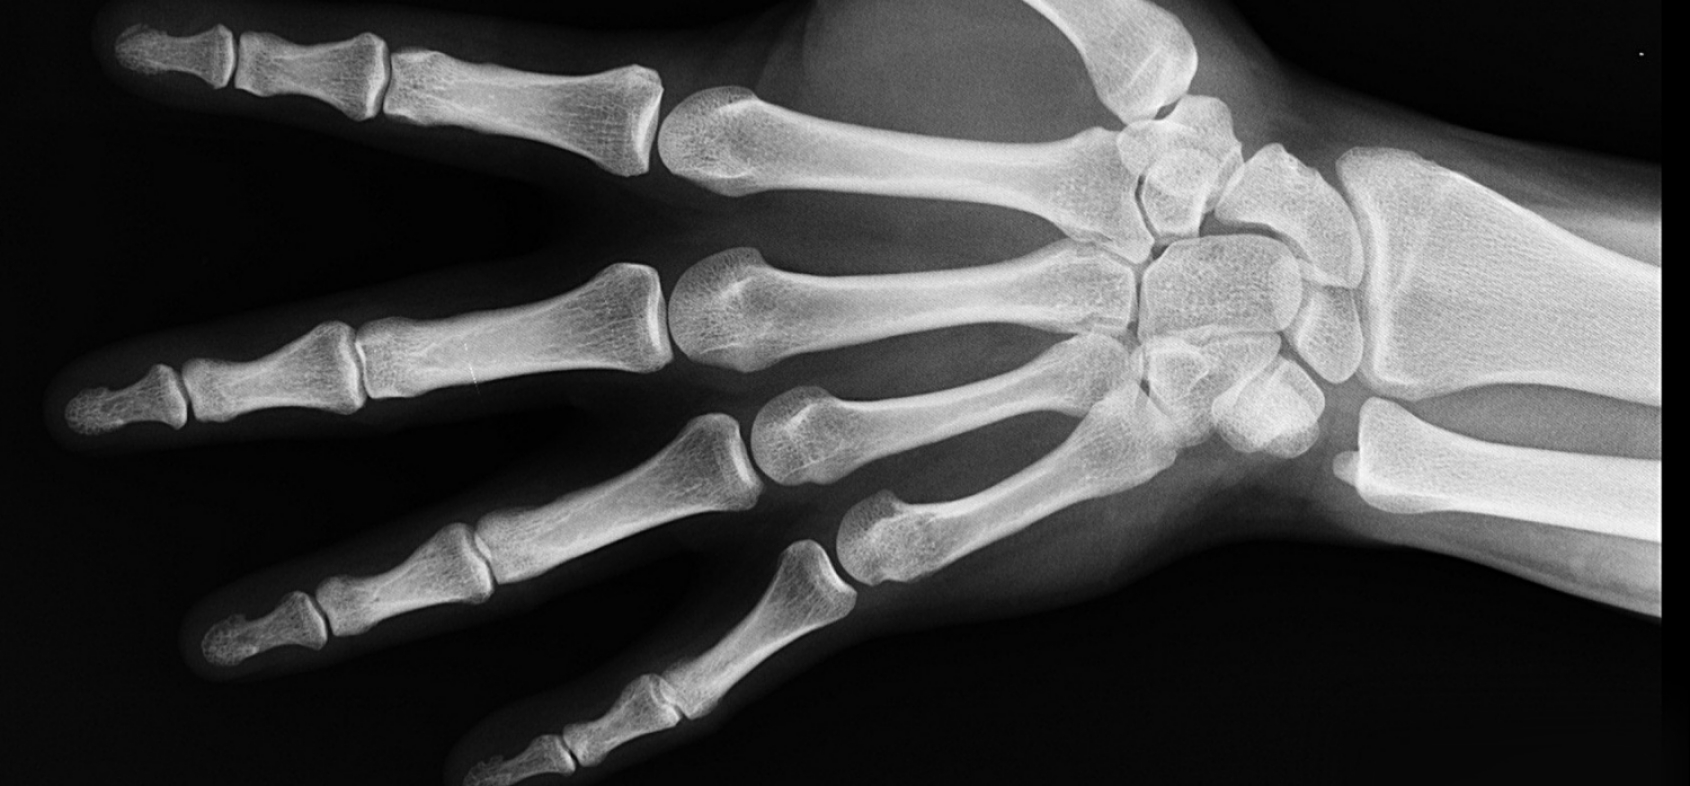

Najprościej mówiąc, jest to choroba polegająca na ubytku masy kostnej, co objawia się łamliwością kości. Nierzadko urazy spowodowane osteoporozą nie są bolesne, co utrudnia wykrycie choroby. W Polsce może na tę przypadłość cierpieć nawet 2 miliony osób. Zdecydowana większość z nich to kobiety, jednak sprawa dotyczy również mężczyzn. Osteoporoza najczęściej występuje po 60. roku życia, a w przypadku kobiet może rozpocząć się nawet po 40. roku życia i ma to związek z okresem menopauzy. Około 80% przypadków stanowi osteoporoza pierwotna, natomiast w reszcie przypadków dochodzi do reakcji organizmu na leki, alkoholizm czy zaburzenia hormonalne.

Mechanizm choroby i objawy

Podstawowym powodem gorszej kondycji kości i ich łamliwości jest niedobór wapnia w organizmie. Wapń, a dokładniej siatka kolagenowa z soli wapnia, odpowiada za strukturę kości i ich wytrzymałość. Zrzeszotnienie kości, czyli osteoporoza, powstaje gdy naturalna przyswajalność wapnia w organizmie człowieka spada. Co za tym idzie, gości nie mają tak gęstej struktury i są podatne na złamania. Proces ten najbardziej dotyczy wrażliwych elementów szkieletu, tj. kręgi w odcinku piersiowo-lędźwiowym, szyjki kości udowej, żeber oraz kości promieniowej. To tam najczęściej dochodzi do bolesnych złamań, które mogą doprowadzić do upośledzenia ruchów motorycznych, w związku z czym osoba chora może stracić możliwość swobodnego chodzenia. Niestety, osteoporoza nie daje objawów. Gdy już dochodzi do złamań, choroba jest w zaawansowanym stadium.